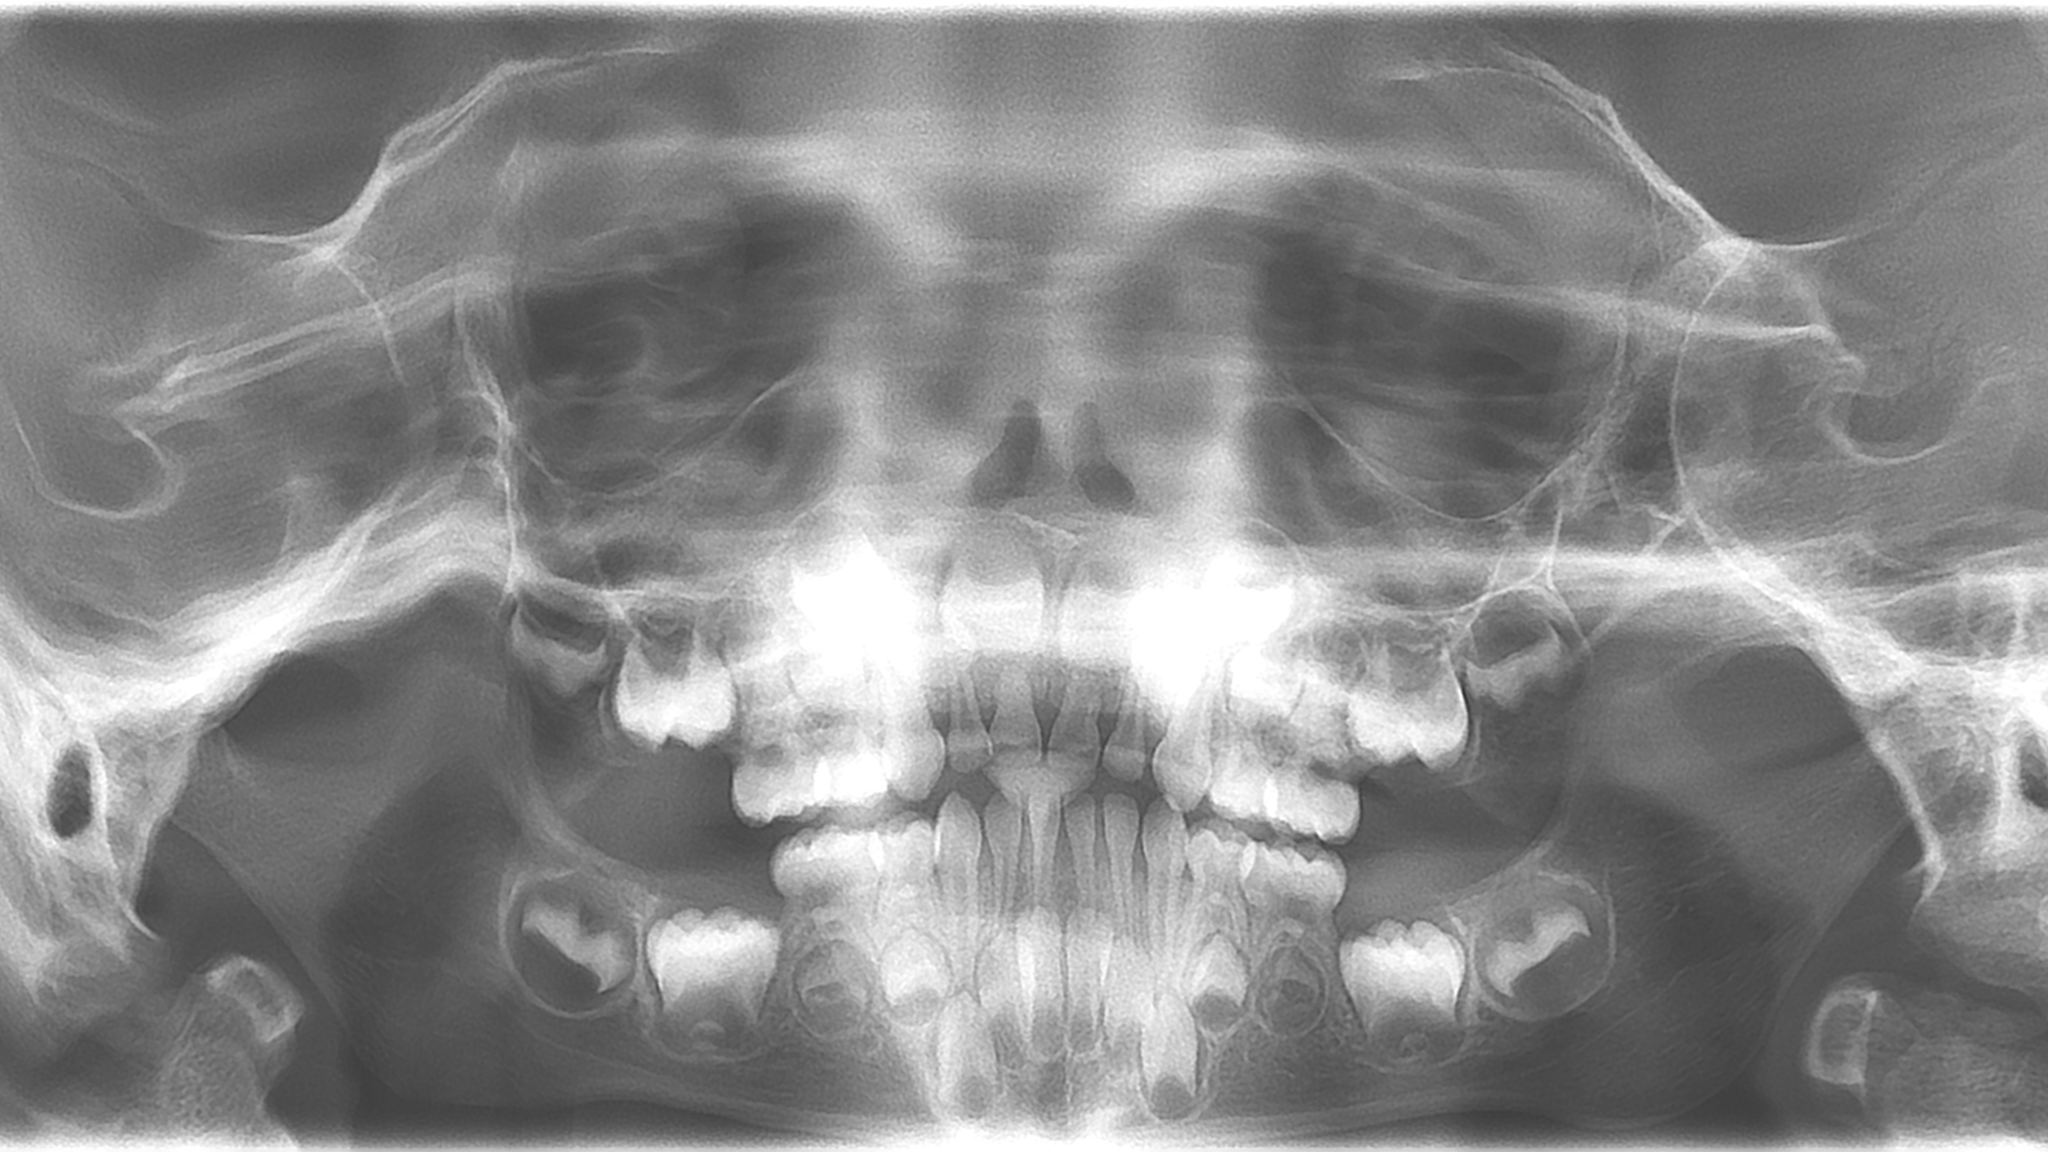

bilan des radiographies début et en cours de traitement